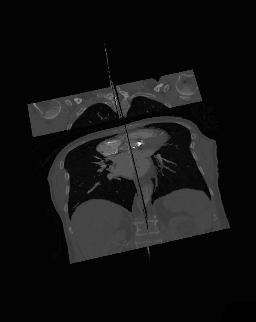

- A final variant on the MPR theme is the generation of a three-dimensional display showing all three orthogonal projections combined so that a defined point of interest locates the intersection of the planes, as illustrated in the following figure:

- The point of intersection is located for illustrative purposes at the centre of the voxel data in the figure above. It can typically be placed at any point in the 3D data using interactive controls. In addition, the perspective used for the rotating sequence can typically be manipulated interactively to improve the visualization of a region of interest. Note that the image sequence illustrated above is one from a myriad of perspectives that can thus be generated. Note also that slice projections (e.g. MIPs) can be combined with this form of display to provide additional perspectives on a feature of interest.